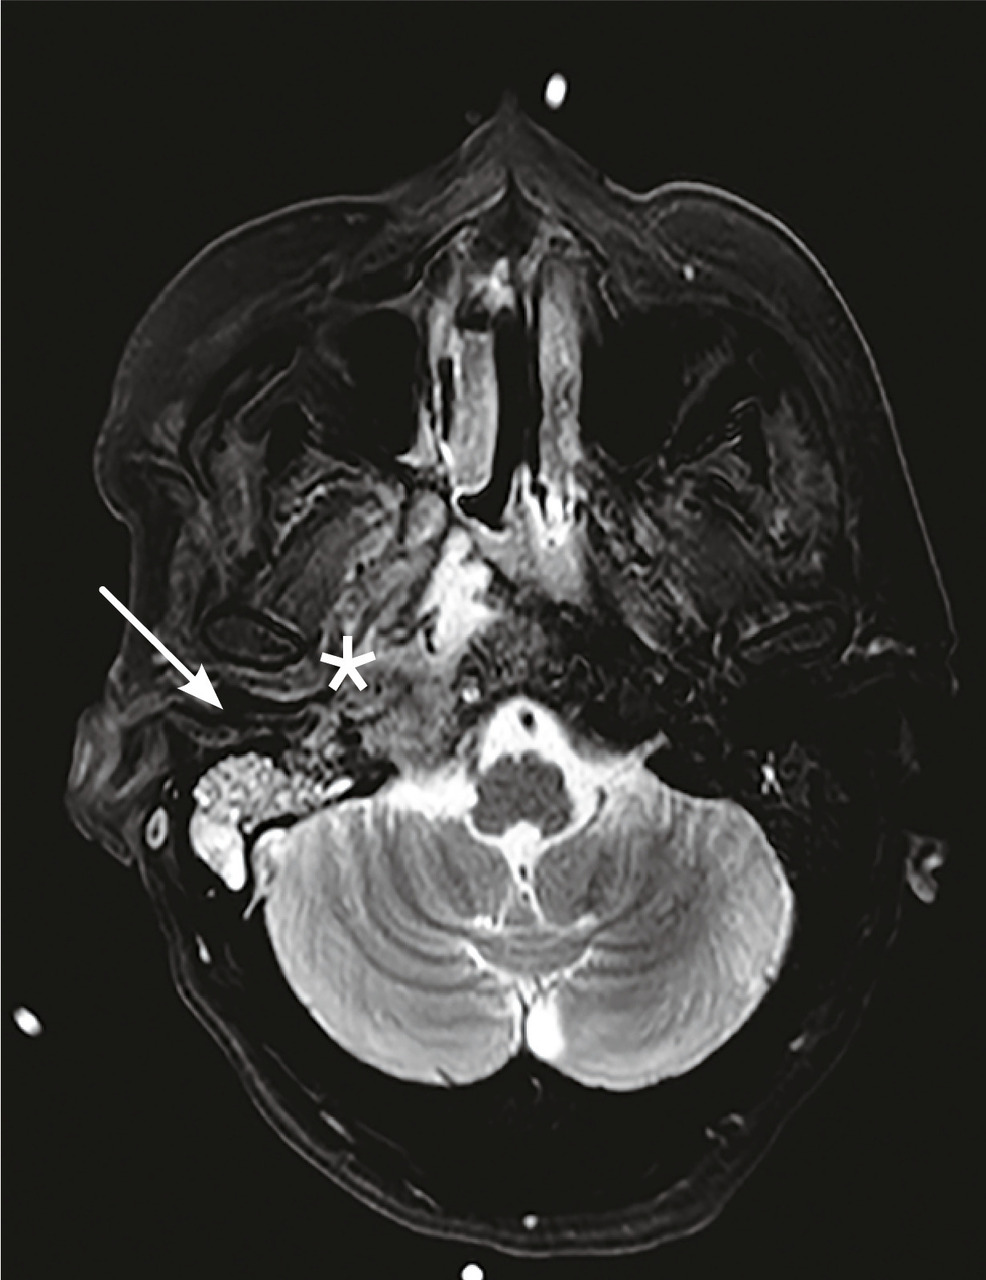

Cette femme de 45 ans était admise aux urgences à la suite d’une hémiplégie gauche. Une imagerie par résonance magnétique (IRM) cérébrale montrait un accident vasculaire cérébral ischémique aigu du territoire de l’artère cérébrale moyenne droite (fig. 1 ) avec occlusion de l’artère carotide droite. Par ailleurs, il y avait un comblant otomastoïdien droit (fig. 2 ) avec collection abcédée parapharyngée homolatérale (fig. 2 ) et thrombose de la veine jugulaire interne droite étendue au sinus sigmoïdien et latéral (fig. 3 ). Après 21 jours d’antibiothérapie intraveineuse combinée à l’anticoagulation, l’IRM de contrôle montrait une recanalisation de la carotide interne et de la veine jugulaire interne.

Le syndrome de Lemierre est une entité rare et potentiellement grave, définie par la survenue d’une thrombophlébite cérébrale touchant la veine jugulaire interne ou ses bran-ches. Il est dû, le plus souvent, à une infection par Fusobacterium necrophorum.1 Le site initial est généralement oropharyngé. En l’absence d’une antibiothérapie précoce et adaptée, ce syndrome peut rapidement évoluer vers une septicémie et à la dissémination par voie hématogène à d’autres sites métastatiques.2 L’occlusion de la carotide interne et la survenue d’un infarctus cérébral sont des complications extrêmement rares et exceptionnelles de ce syndrome.